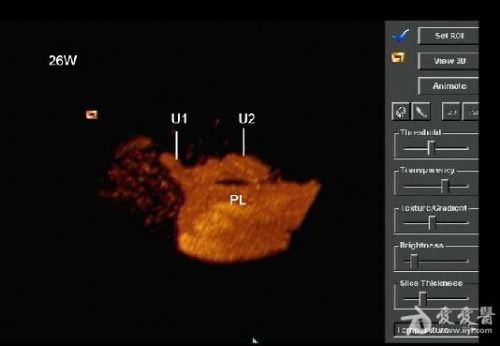

孕妇,26岁。一月前在当地医院超声检查示:双胎妊娠,其中一胎存活(BPD:2.6cm,PL:0.9cm),另一胎死胎并颈部淋巴水囊瘤(BPD:1.9cm,PL:0.9cm)。

是双胎,其中畸形的那个明显没有上半身及头部,只有下半身和一点点短小的左上肢。